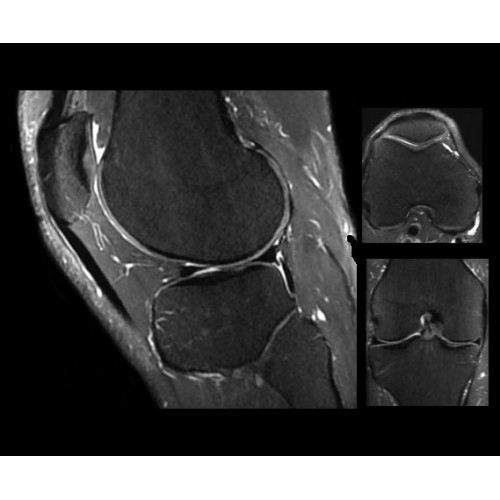

Система SIGNA PET/MR предлагает впечатляющие клинические возможности и открывает доступ к наиболее полным пакетам программных приложений.

• Приложения для коррекции артефактов движения — используйте наиболее широкий набор инструментов, таких как PROPELLER, PROMO и навигаторы Pencil Beam, позволяющих снизить влияние непроизвольных или физиологических движений на качество изображений.

Стандартный пакет приложений SIGNA Works позволит вам достичь желаемых результатов в клинической практике благодаря набору высокоэффективных средств визуализации. Программные приложения, входящие в состав данных клинических пакетов, включают широкий спектр контрастов, функции обработки 2D- и 3D-данных, а также возможность коррекции артефактов движения. SIGNA Works предоставляет набор инструментов, необходимых для проведения эффективного клинического исследования.